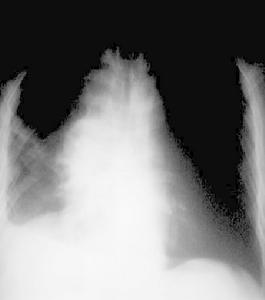

惡性胸腔積液CT圖在體格檢查時可發現患側呼吸運動減弱,肋間隙飽滿,氣管向健側移位,積液區叩診為濁音,呼吸音消失。